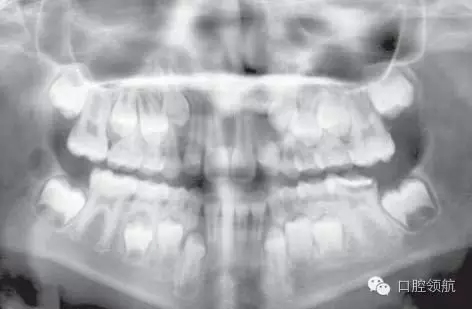

這是一個全科牙醫(yī)轉(zhuǎn)診的病例。該名女性患者I類錯牙合,輕度擁擠,LL6嚴(yán)重齲壞,無法保留。患牙有間歇性的夜間痛,使其在夜間痛醒。圖2.8是由全科牙醫(yī)提供的最近的全景片。

圖2.8

全景片上最主要的特征有哪些?

● 混合牙列。

● 切牙已萌出。

● LL6嚴(yán)重齲壞;可見遠(yuǎn)中根根周感染,有臨時修復(fù)體存在。

● 除第三磨牙以外所有恒牙都存在(LR8可見早期牙胚發(fā)育)。

● 第二磨牙的牙冠發(fā)育完成。下頜的根間區(qū)域已開始發(fā)育。